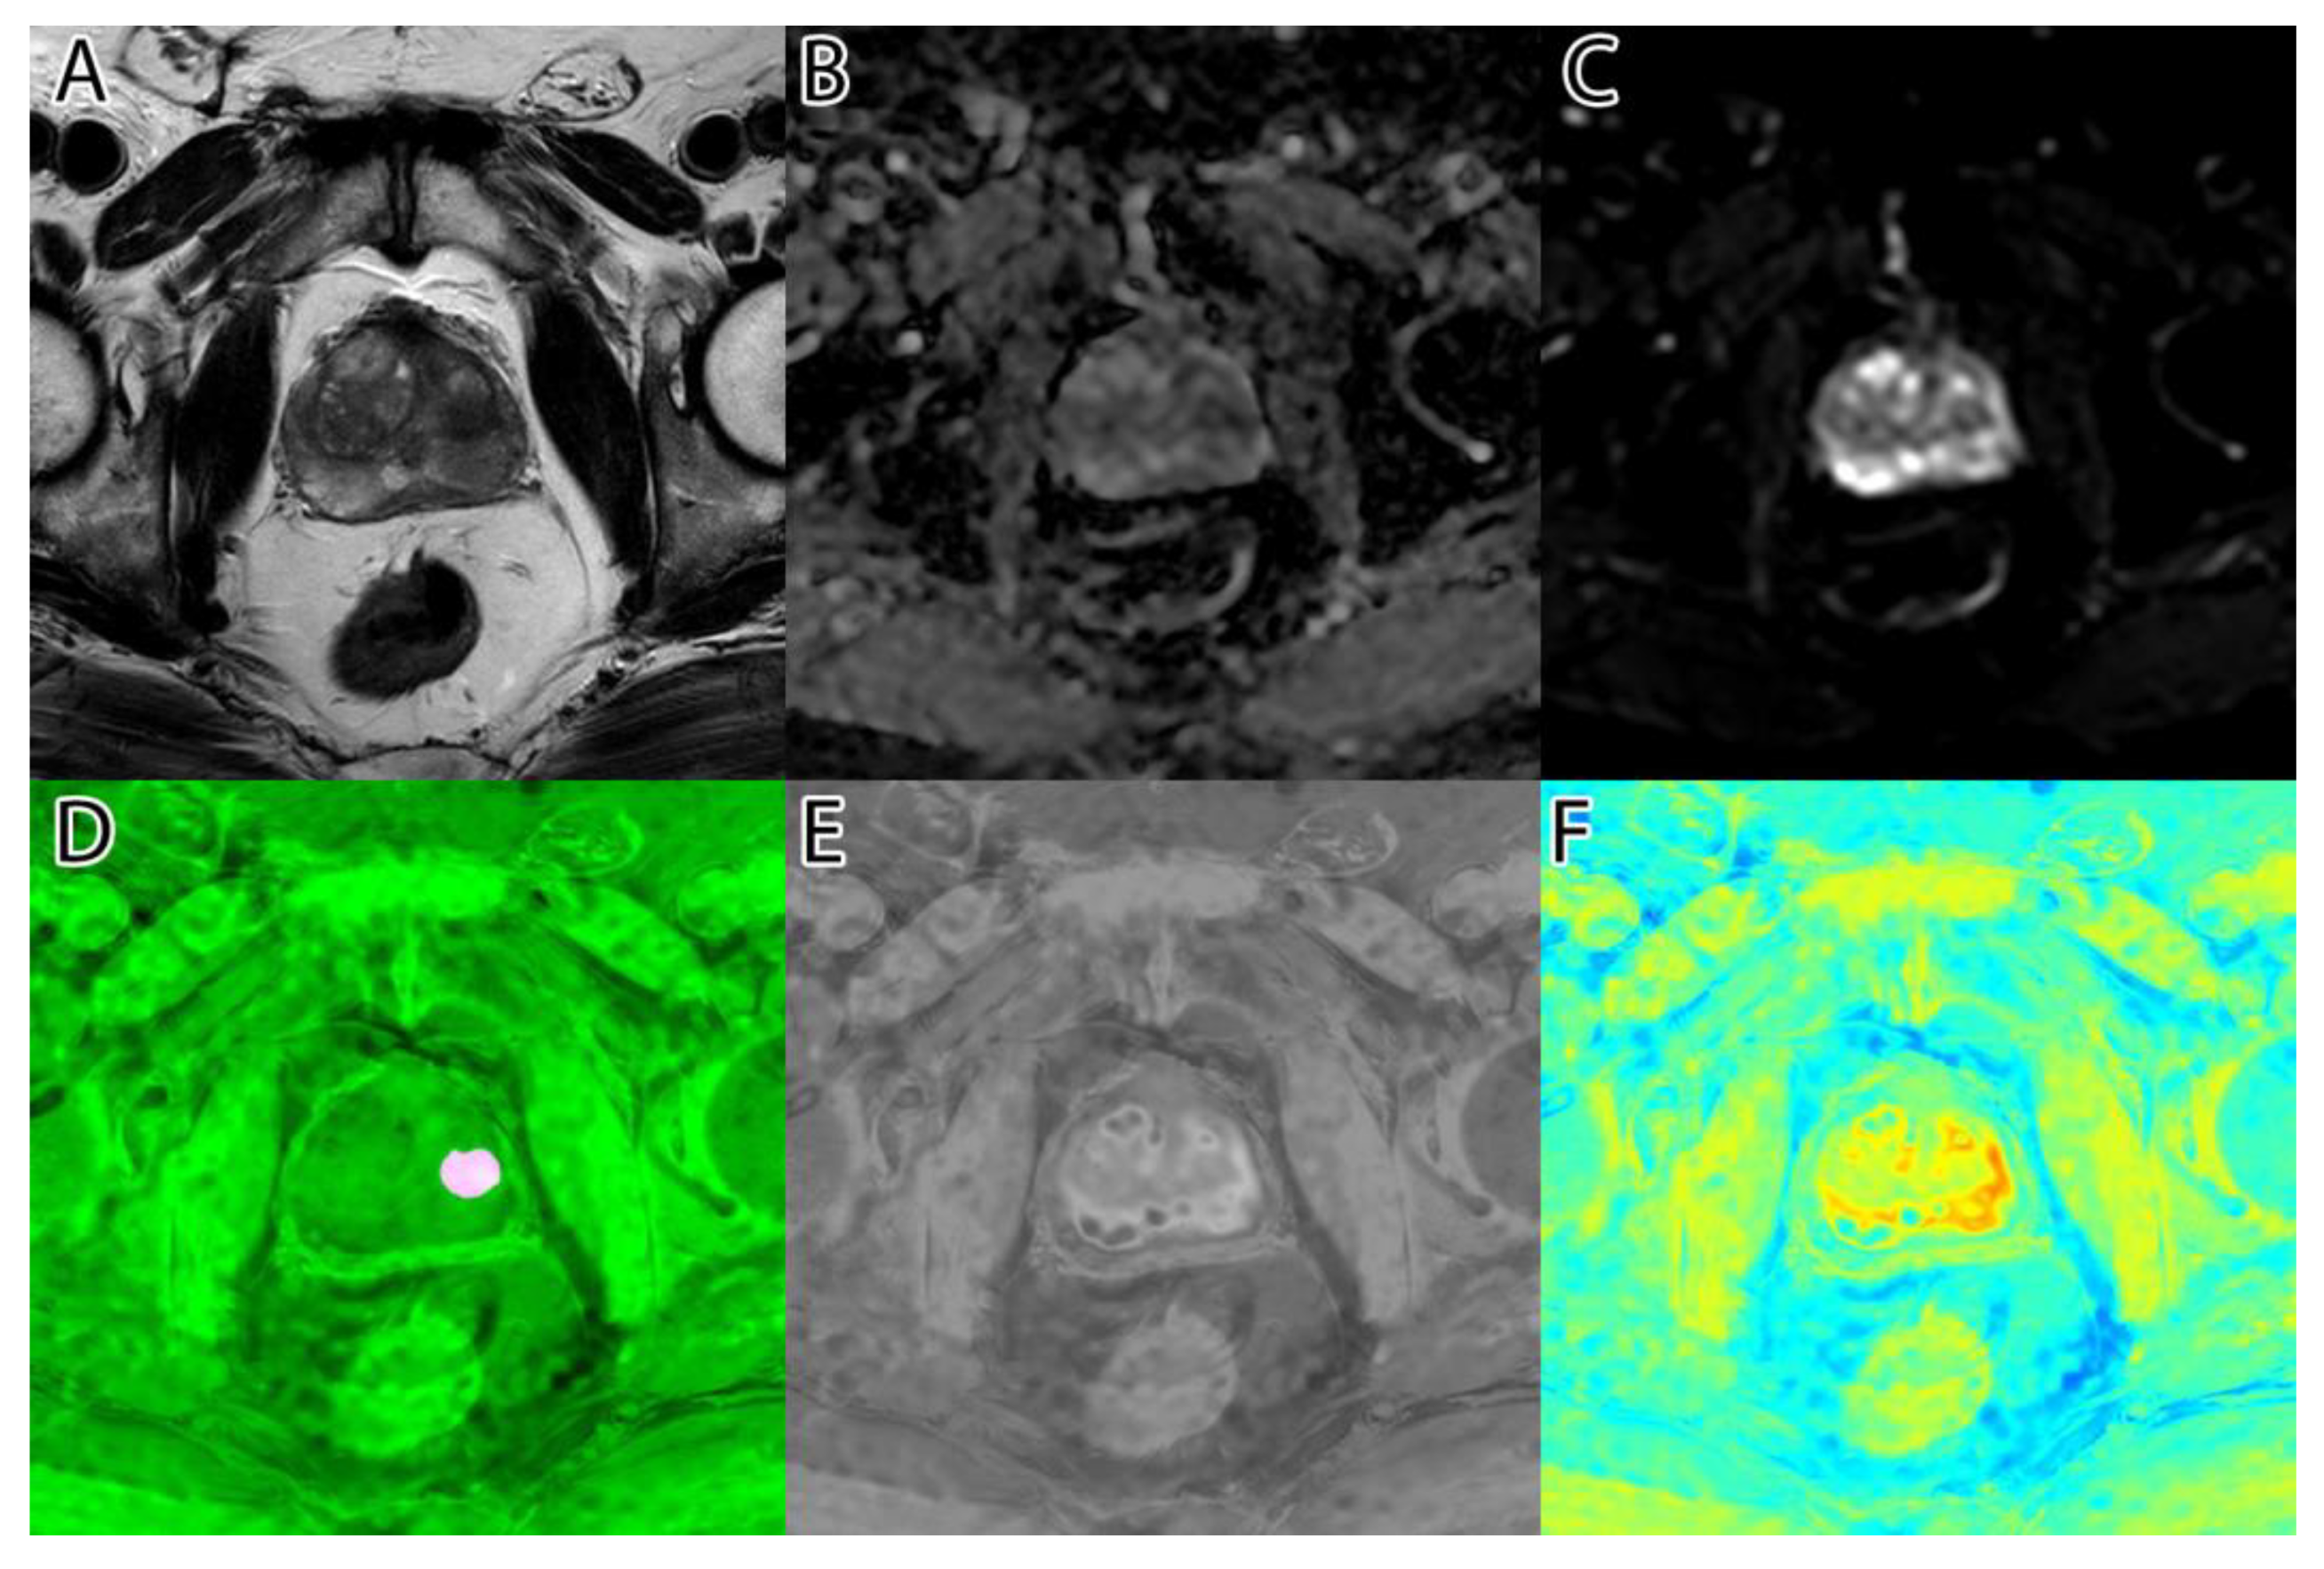

The sixth and final step was to compute the final intensity mask by subtracting the square root from the square sum of the alpha–beta channels and subtracting the resulting value from the luminance. The resulting intensity image can be seen in Figure 2B and Figure 3B. By adding the ‘jet’ color map to it, we obtained a colored intensity map that highlights the tumoral areas, as seen in Figure 2C and Figure 3C.

Figure 2. PI-RADS 2 patient: (A)—T2WI; (B)—ADC; (C)—DWI; (D)—RGB fused image; (E)—grayscale tumor intensity image; (F)—‘jet’-mapped tumor intensity image.

Samples of the computed tumor intensity images can be seen in Figure 2 for a PI-RADS 2 patient and in Figure 3 for a PI-RADS 5 patient. Notice the difference in “jet” intensity between the control patient and the patient with extraprostatic invasion.